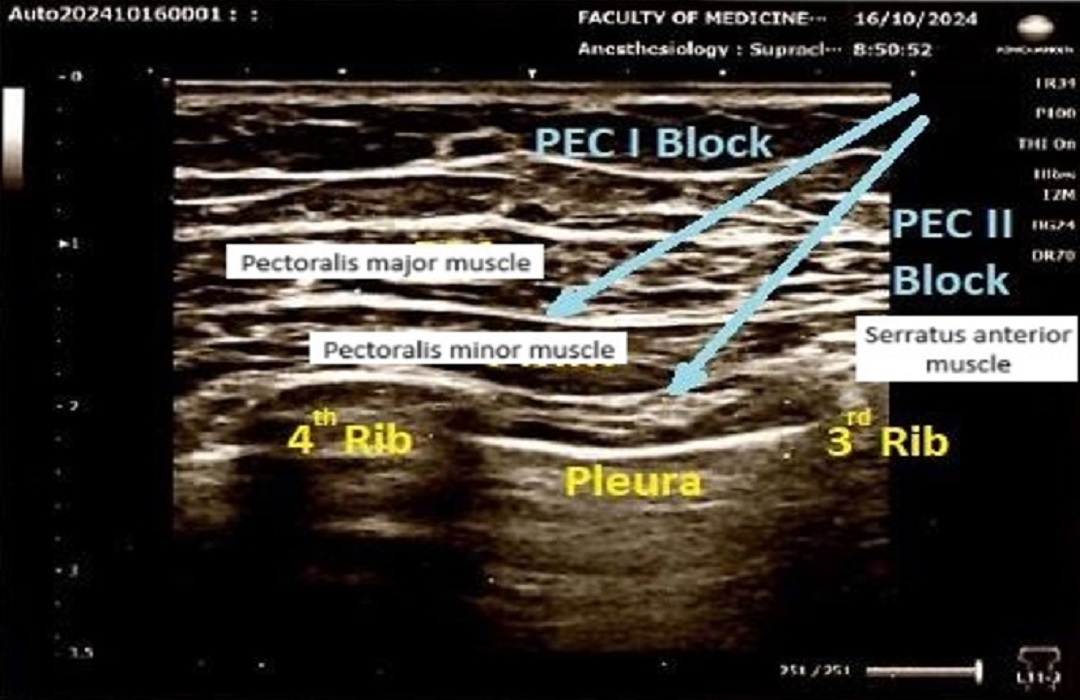

• Comparison of Acute Postoperative Pain Between Preemptive Ultrasound-Guided Pectoral Nerve Block and Intraoperative Pectoral Nerve Block in Patients Undergoing Mastectomy